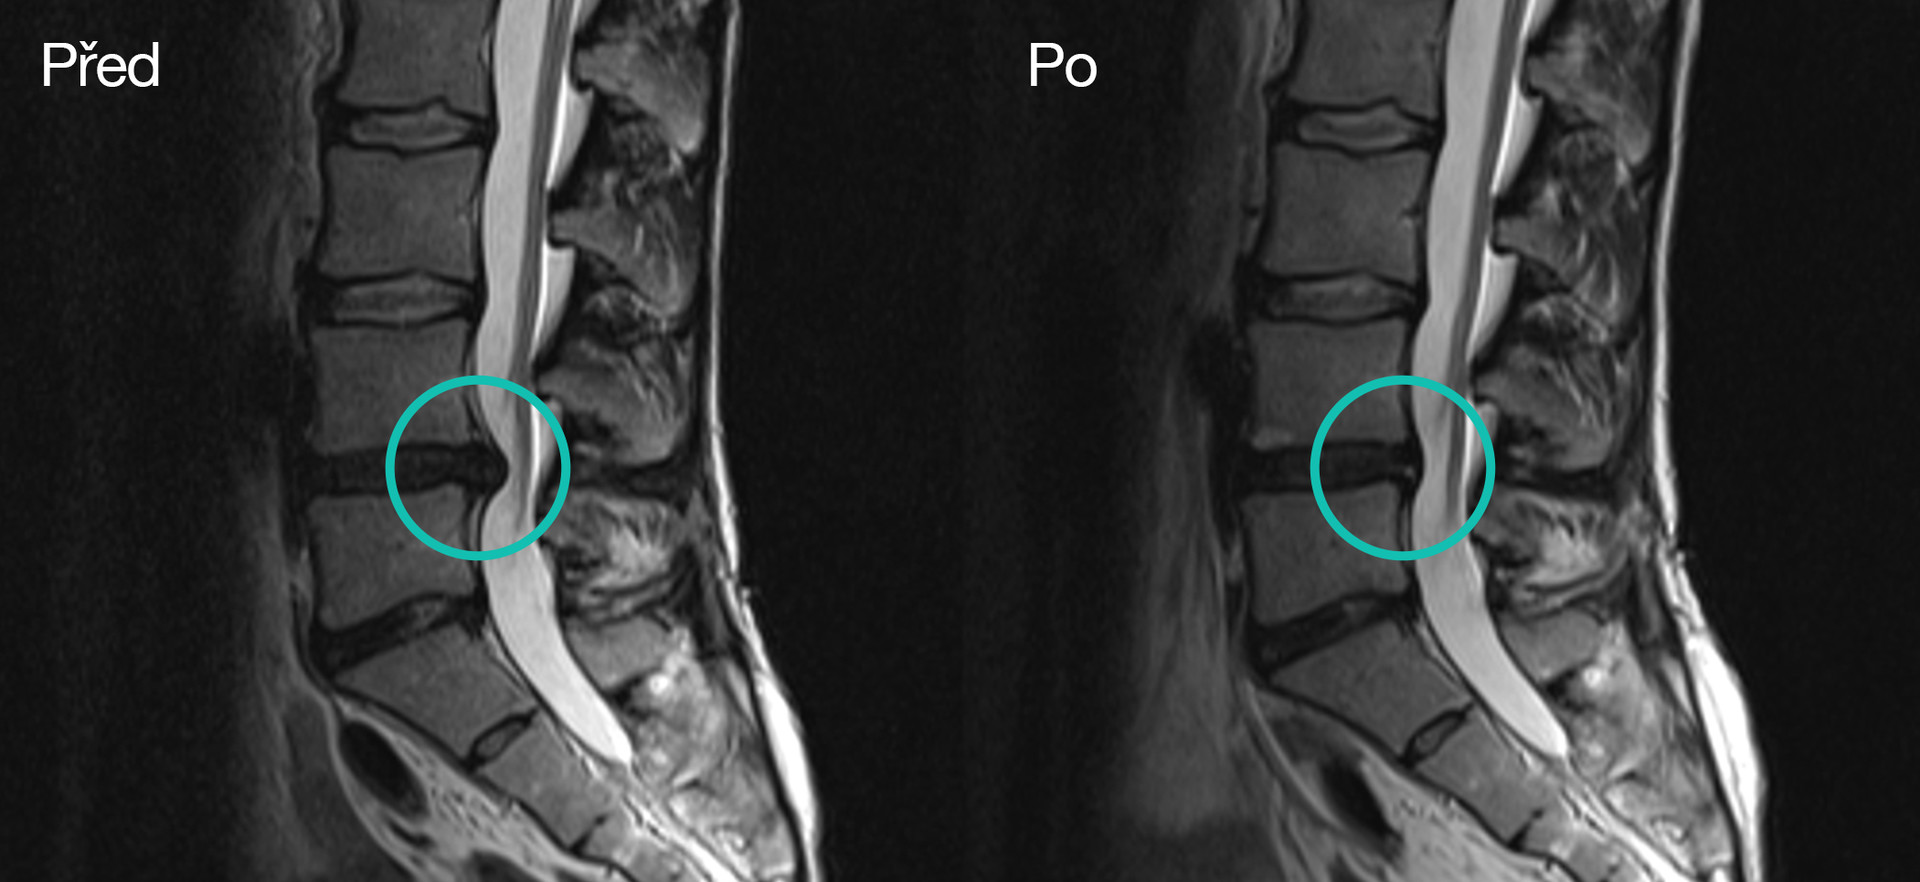

페트라는 첫 임신 중에 왼쪽 엉덩이쪽에 고관절 통증이 오기 시작했습니다. 그녀는 MRI 검사를 받았고 두 개의 추간판(L4/L5 및 L5/S1)에 손상이 있는 것으로 진단을 받았습니다. 이후 그녀는 손상된 L5/S1 디스크를 제거하는 수술을 받았습니다. L4/5 디스크는 수술하지 않았고, 수술 후에도 환자는 계속해서 통증으로 불편함을 겪었습니다.

페트라는 멀리 살았기 때문에 체류 형태의 단계적 치료를 선택했습니다. 매 체류 기간은 일주일 동안 지속되었으며 그녀는 총 세번의 체류형 치료를 완료했습니다. 3월에 처음으로, 6월에, 그리고 10월에 마지막으로 치료를 마쳤습니다. 그녀의 문제는 점차 해결되었습니다. 치료 1년 후에는 통증이 전혀 없었고, 다시 편안하게 잠을 잘 수 있었으며, 걷는 것도 더 이상 고통스럽지 않았습니다. 후속적으로 MRI를 시행하여 L4/5 디스크의 치유와 디스크 탈출의 재흡수를 확인할 수 있었습니다.